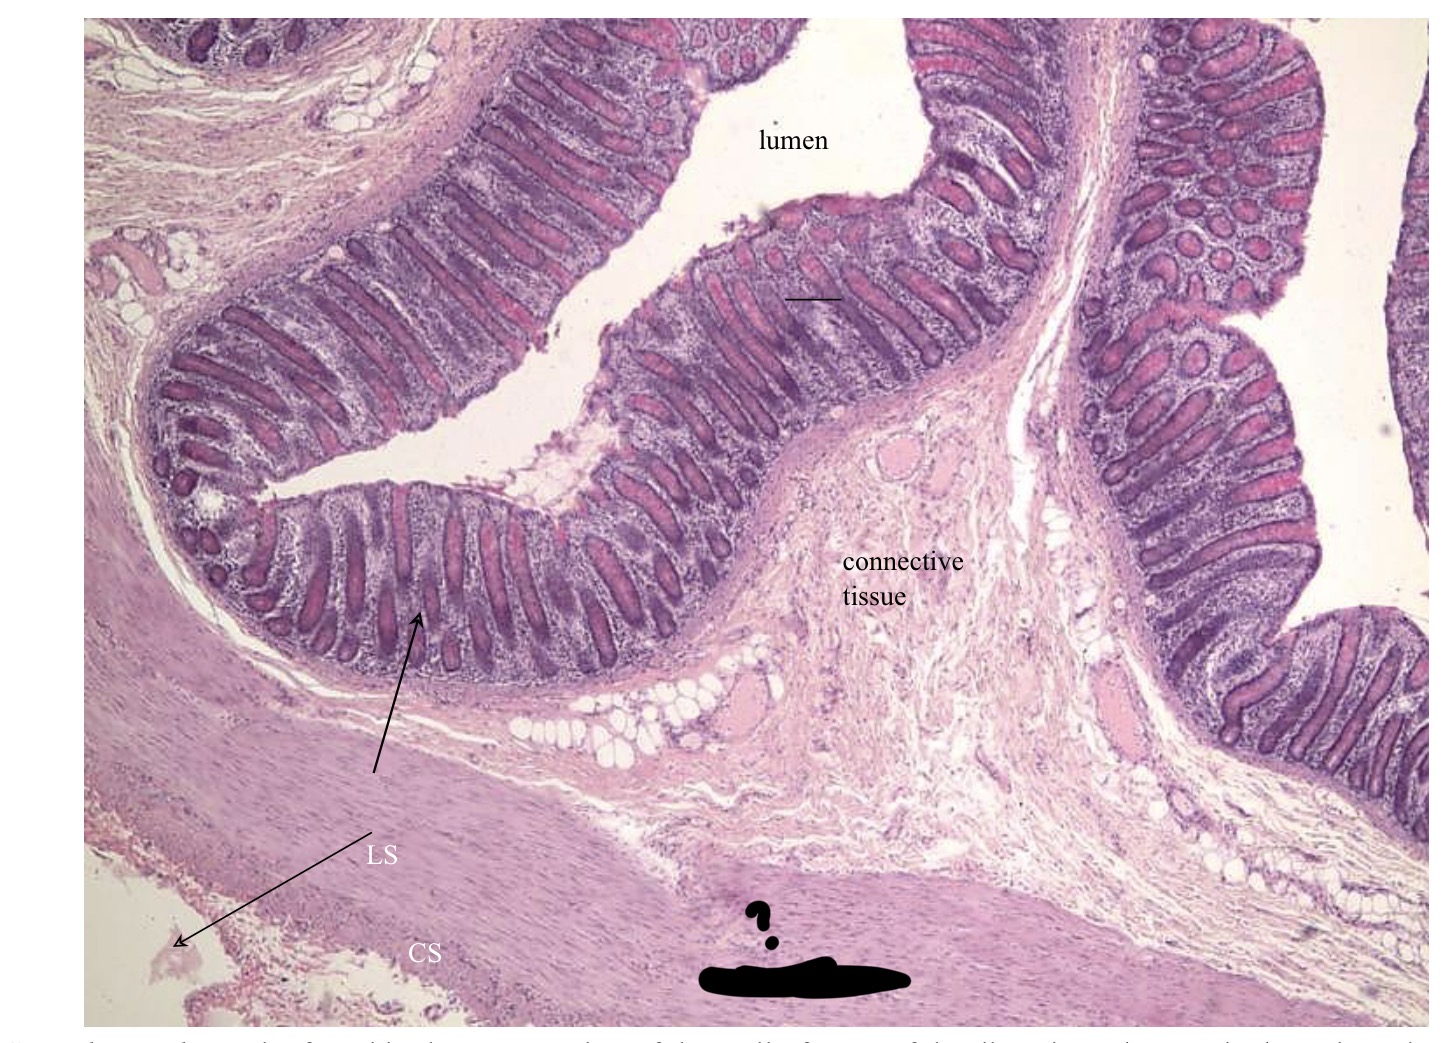

What kind of muscle tissue is this? Label. Where is it found in the body?

Smooth muscle

Blood vessels (veins, arteries), esophagus, intestines